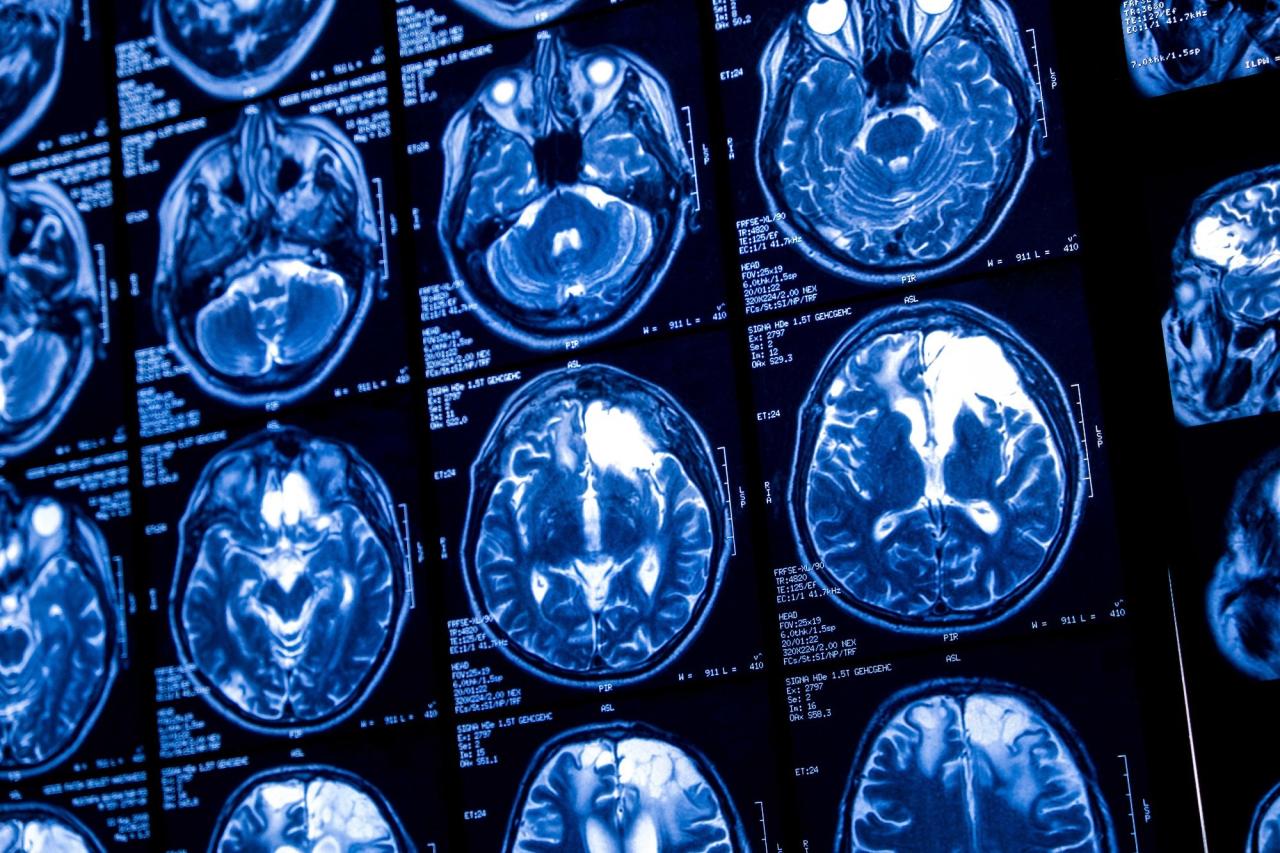

最近发表在《Biology Methods and Protocols》上的一项研究中,研究人员探讨了使用卷积神经网络(CNNs)和迁移学习来提高磁共振成像(MRI)扫描中脑肿瘤检测的效果。

本研究结合了基于 CNN 的模型和迁移学习技术,探讨了使用 MRI 扫描对脑肿瘤进行分类。

研究人员使用了一个主要数据集,该数据集包括显示三种胶质瘤(星形细胞瘤、少突胶质细胞瘤和少突星形细胞瘤)以及正常脑图像的 T1 加权和 T2 加权后对比 MRI 图像。